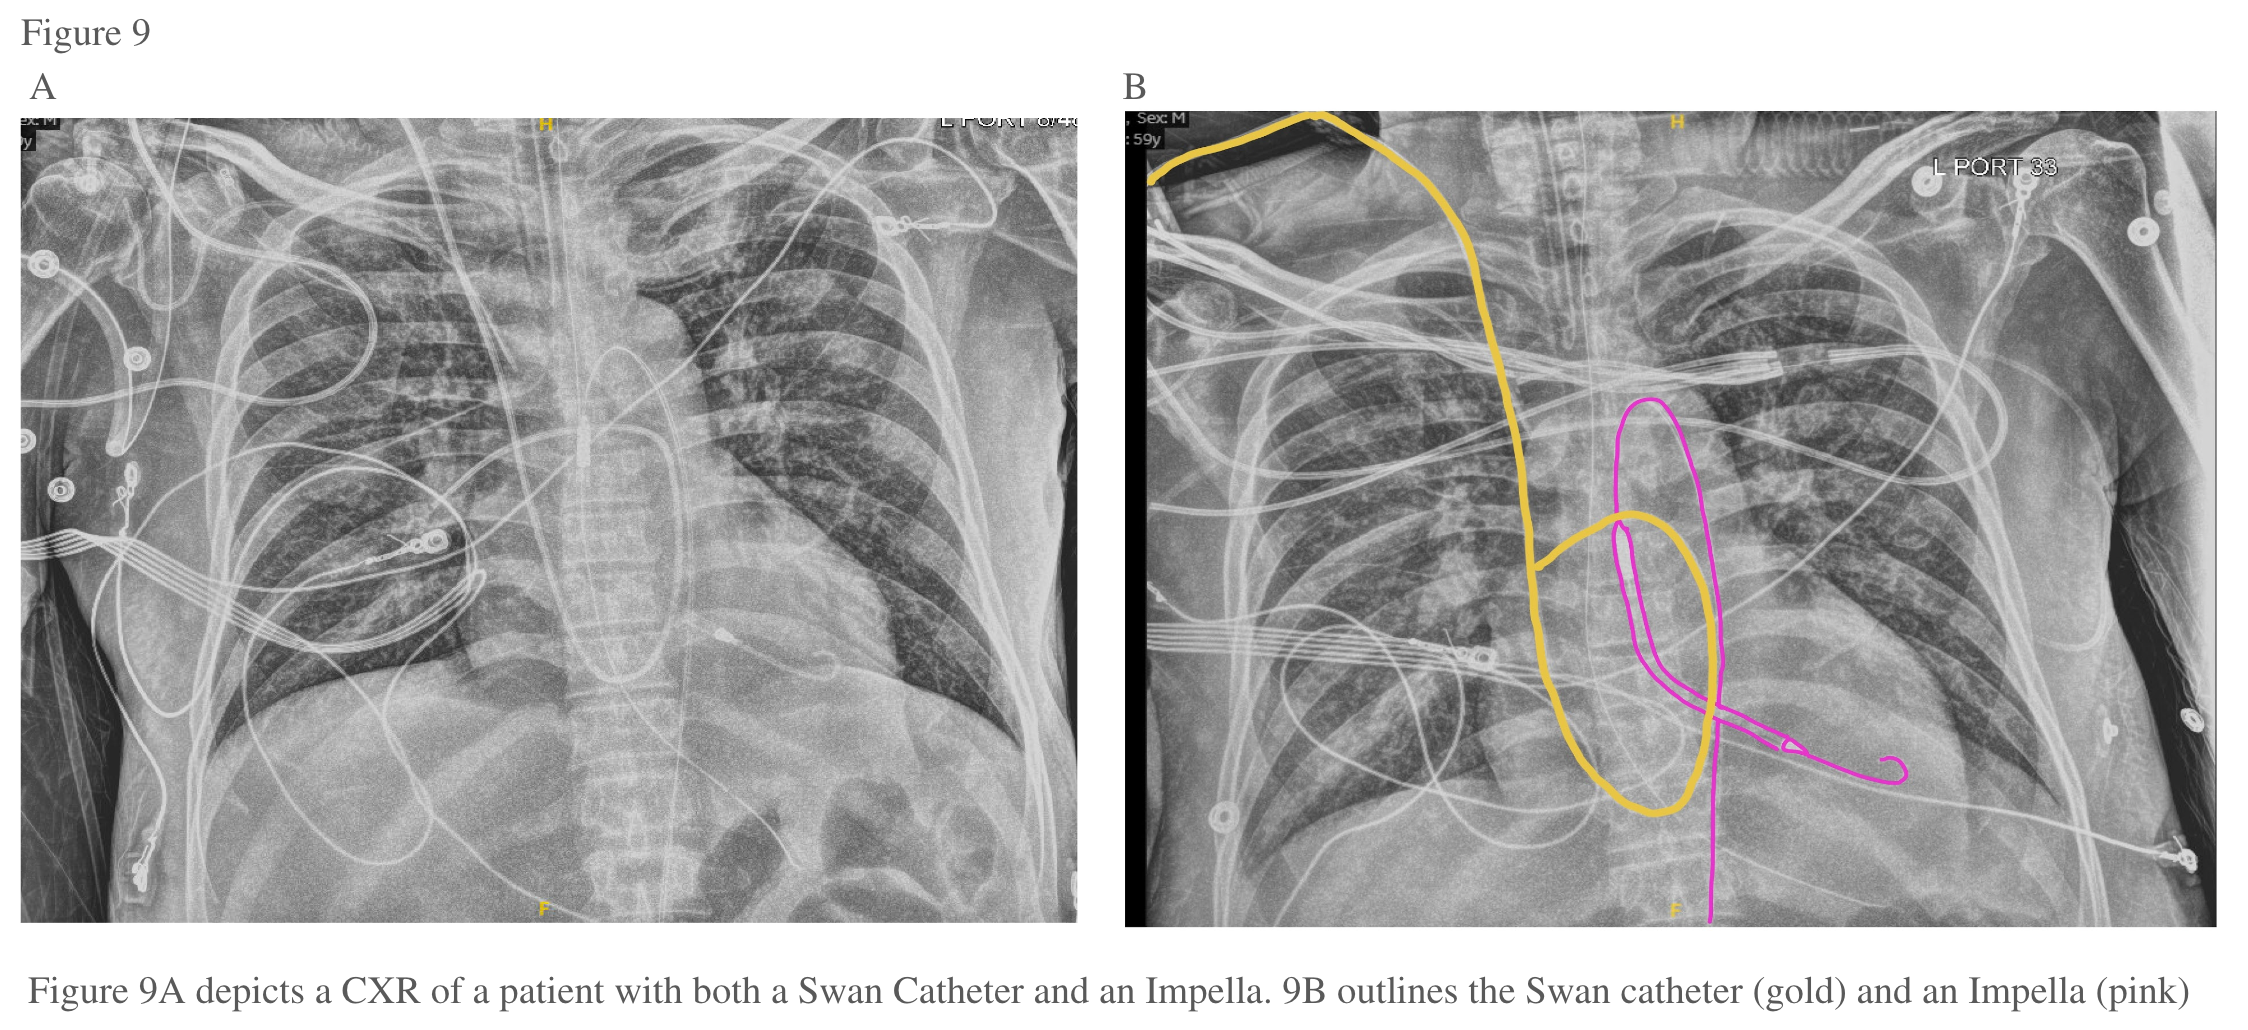

Positioning of the Catheter–Should be assessed with CXR daily:

Ensure proper placement of the catheter at least daily with a CXR. Note how far the catheter is in.